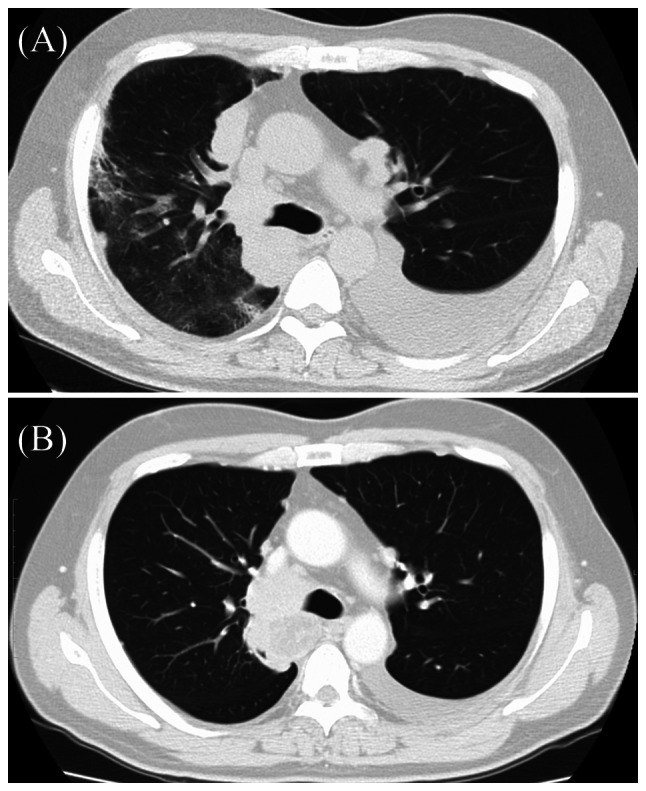

The present study determined the clinical types of DLI according to the findings on chest CT (Table V and Fig. 1). In Group C+P and Group C, DAD was observed in two patients each. The cancer treatment was discontinued in all four patients with pneumonia of DAD, and two of them succumbed to pneumonia. By contrast, the pattern of DLI in all the patients of Group P was OP. In regard to the prognosis in patients with DLI, chemotherapy was discontinued and best supportive care (BSC) initiated in 6 out of the 8 patients in Group C+P and all patients in Group P. However, the cancer therapy could be continued despite the development of DLI in ~50% of the patients of Group C. A case of DLI in the C+P group, classified as DAD, is shown in Fig. 2.

Figure 2.

CT image in a patient with drug-induced lung injury. (A) Image at the onset of Pneumonitis. Pneumonitis with DAD pattern in a 58-year-old man demonstrated diffuse ground-glass and consolidation after receiving 8 doses of nivolumab and then 13 doses of cetuximab. Steroid treatment brought him lull, but further anticancer drug treatment could not be continued. (B) Image taken 4 months before the onset of pneumonitis showed no evidence of pneumonia. CT, compute tomography; DAD, diffuse alveolar damage.